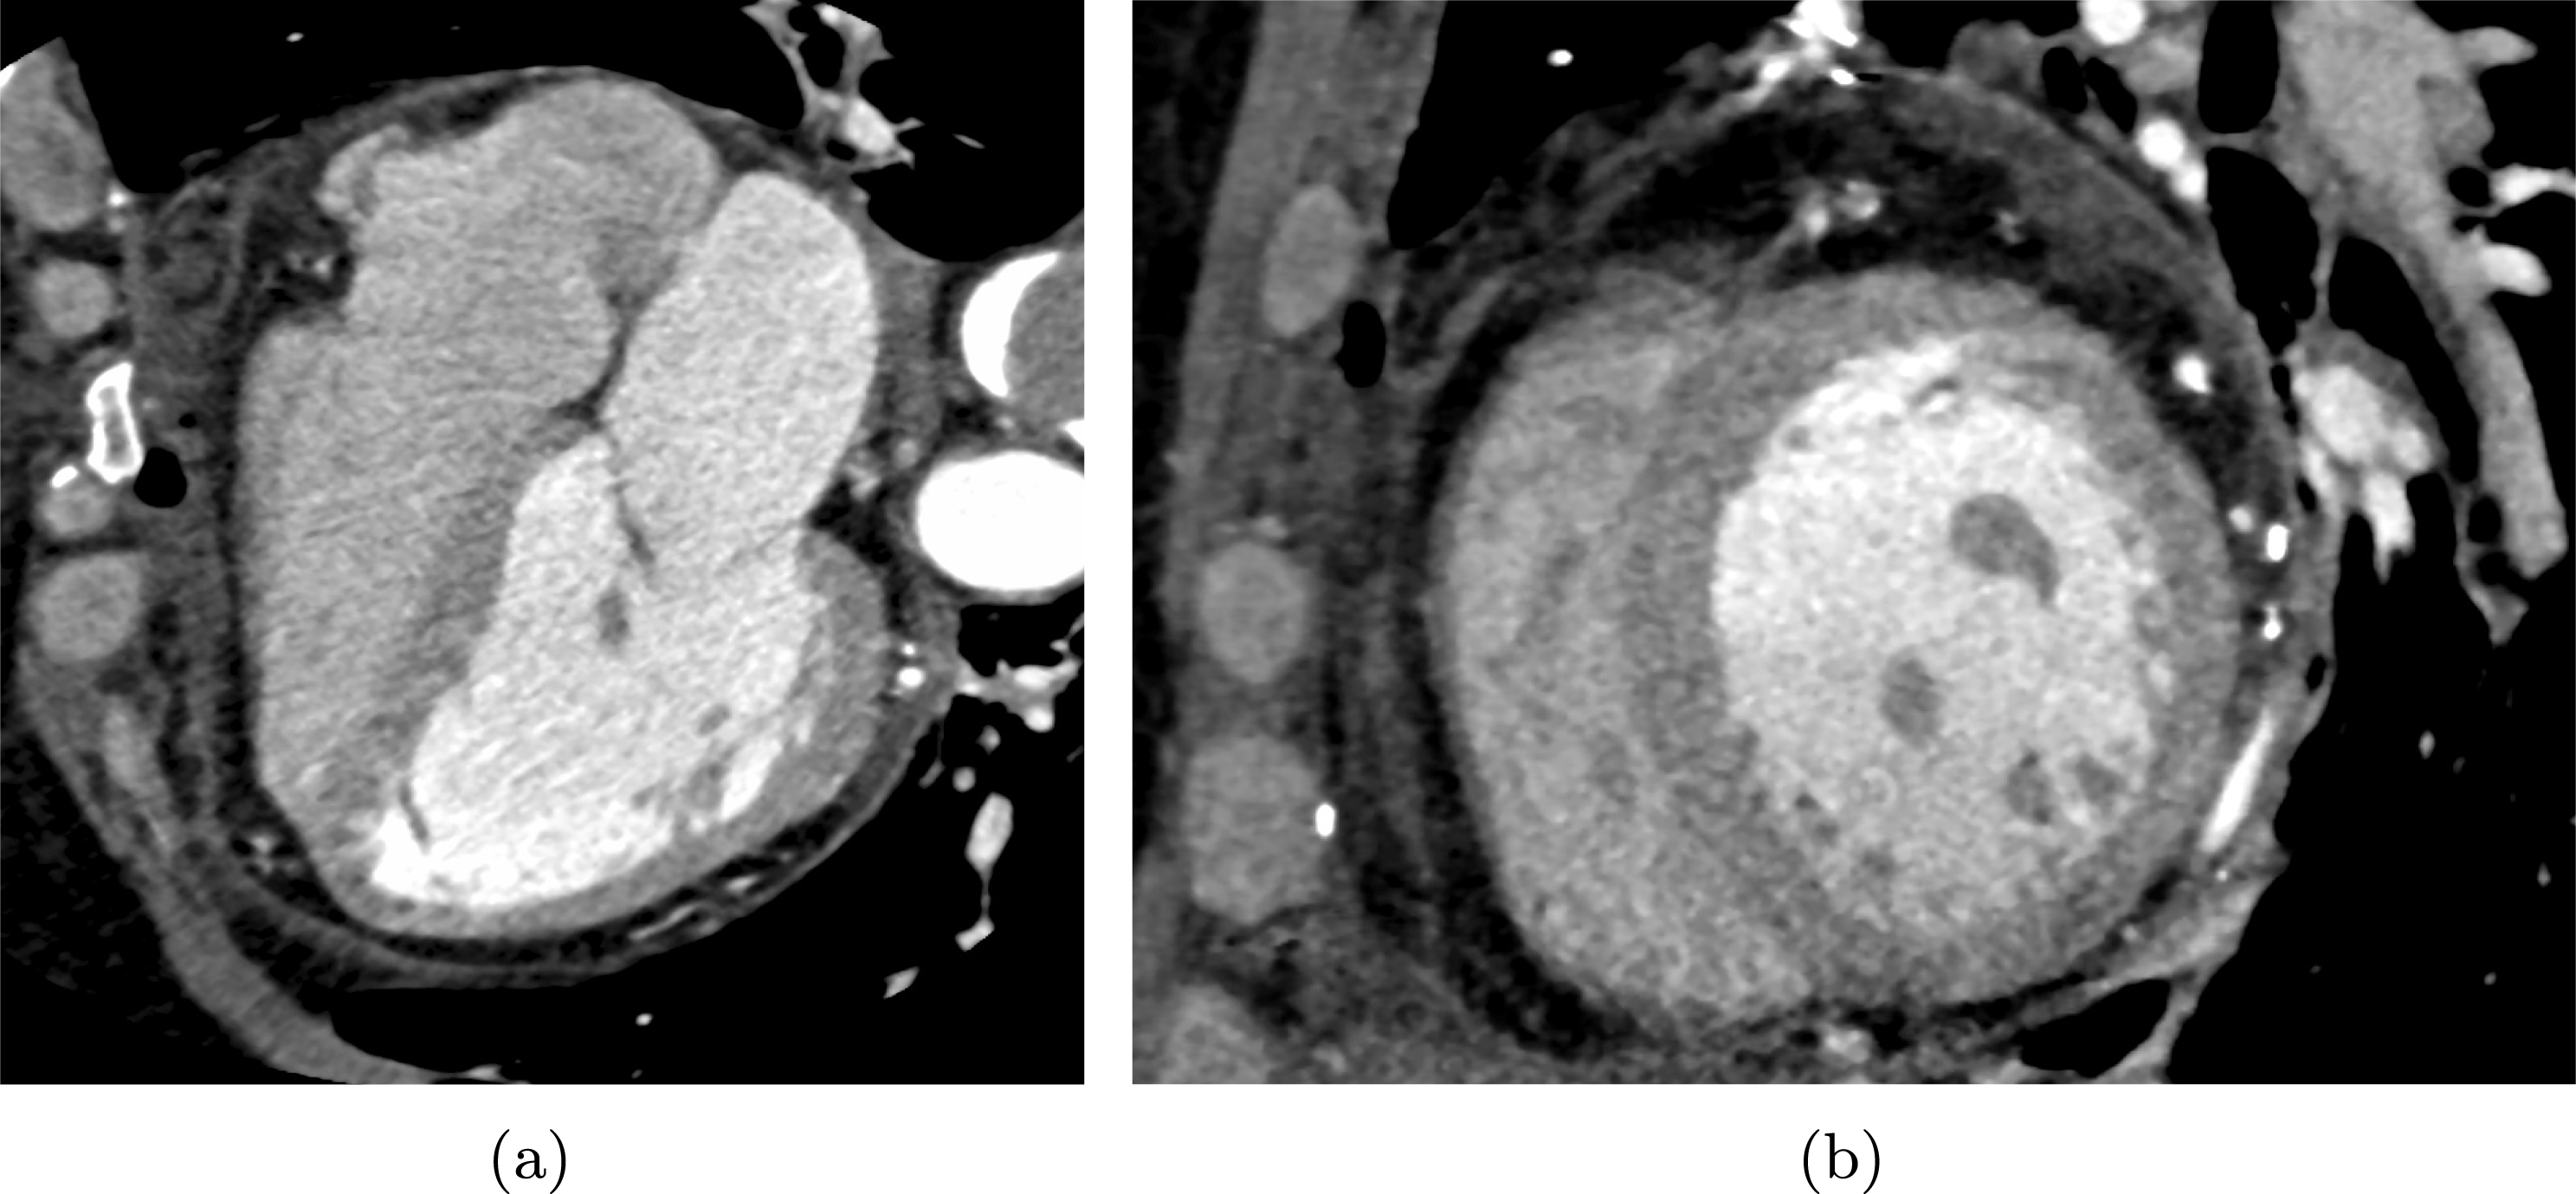

Figure 4.1. Representation of the fluid domain (a) and structure domain (b). The fluid domain illustrated is that of an abdominal aorta in the presence of an aneurysm, reconstructed from CTA images. The structure domain was obtained via extrusion of the fluid domain.